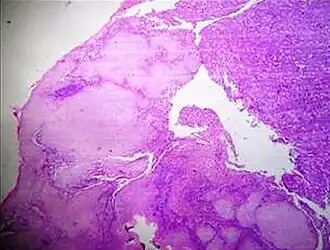

![Tearing artifacts, such as can be caused by: - Microtomy with a nick or blemish in the knife edge.[5] - Traction of the sections. - Too much or too little alcohol dehydration.[5] - Sectioning calcified parts, which can be decalcified or removed.[5]](./_assets_/Microscopy_of_liver_parenchyma_with_tearing_artifacts.jpg)